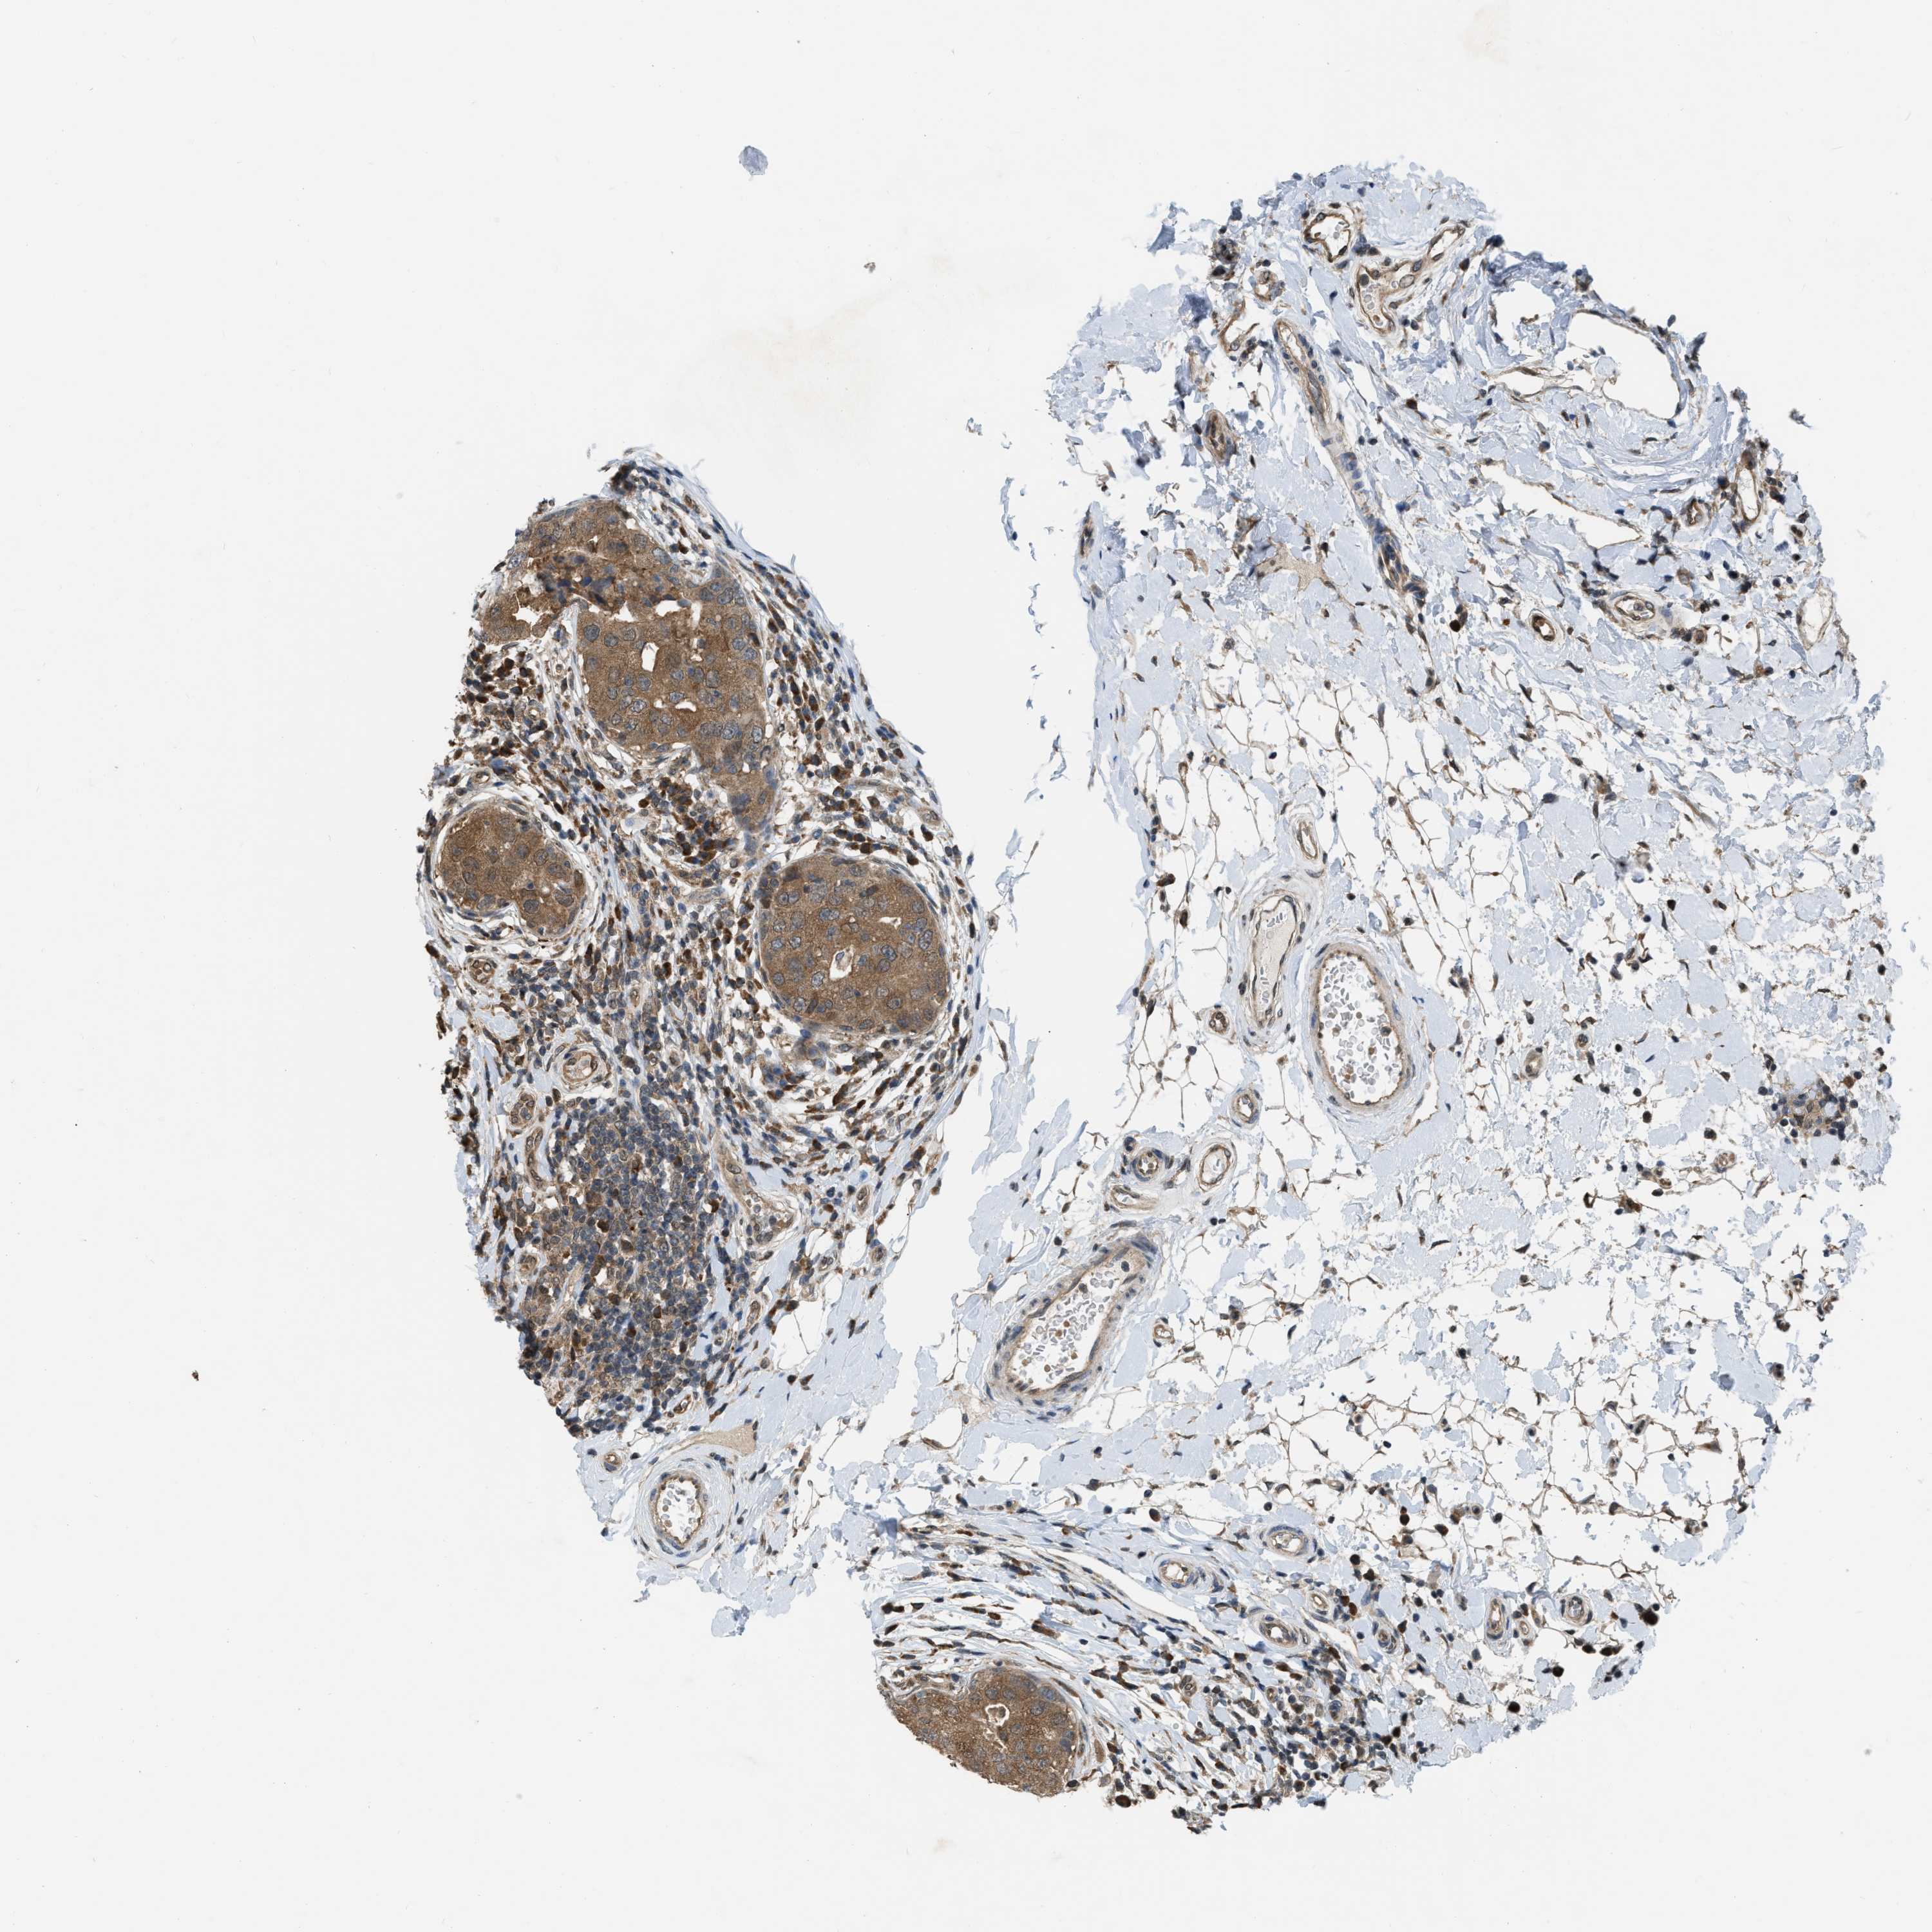

BRCA TCGA BRCA VALIDATION PROTEIN EXPRESSION